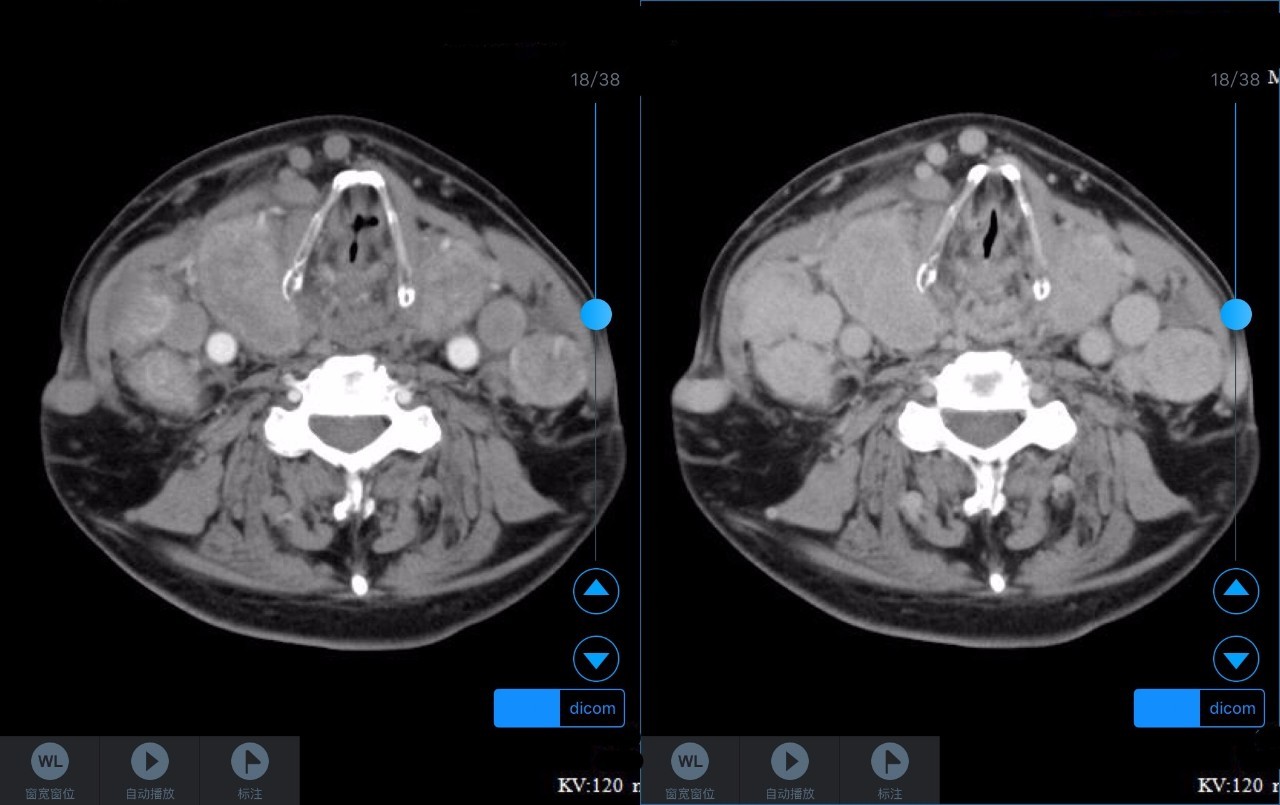

▼患者CT平扫(右)及增强CT(左)检查报告资料

Z主任 甲状腺肿大,内见弥漫多发结节,界限不清,甲状腺包膜毛糙。双侧颈部、锁骨上、纵隔多发肿大淋巴结,病变均强化明显,密度不均,边缘毛糙,考虑甲状腺恶性肿瘤伴多发淋巴结转移,或甲状腺内也是转移瘤。Castleman病多灶者少见,一般病变边缘光整,也不会累及甲状腺。建议穿刺活检。 C主任 双侧甲状腺肿大,密度不均,不均匀强化,甲状软骨未见明显骨质破坏气管右侧壁受压;双侧颈部多发肿大淋巴结,不均匀强化;考虑为甲状腺恶性占位性病变伴双侧颈部淋巴结转移,建议组织学进一步检查。 声明:以上资料均来自和缓名医平台的真实案例,为保护用户隐私,均用化名代替。资深医师Z咨询反馈